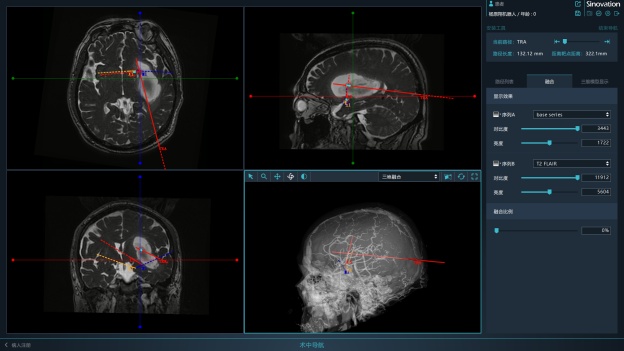

经过精密的术前准备与讨论,侯立军主任根据独创的国际创新理念与术式,为老杨实施了机器人辅助下枕部入路颅内血肿穿刺引流术。手术机器人的机械臂经过精准的计算与术前计划,准确的避开功能区,穿刺到达血肿,将血肿完全吸除。整个手术过程仅半小时,出血量微乎其微。

术前设计手术规划

左:术前设计的精准穿刺路径

右:术后可见血肿完全清除